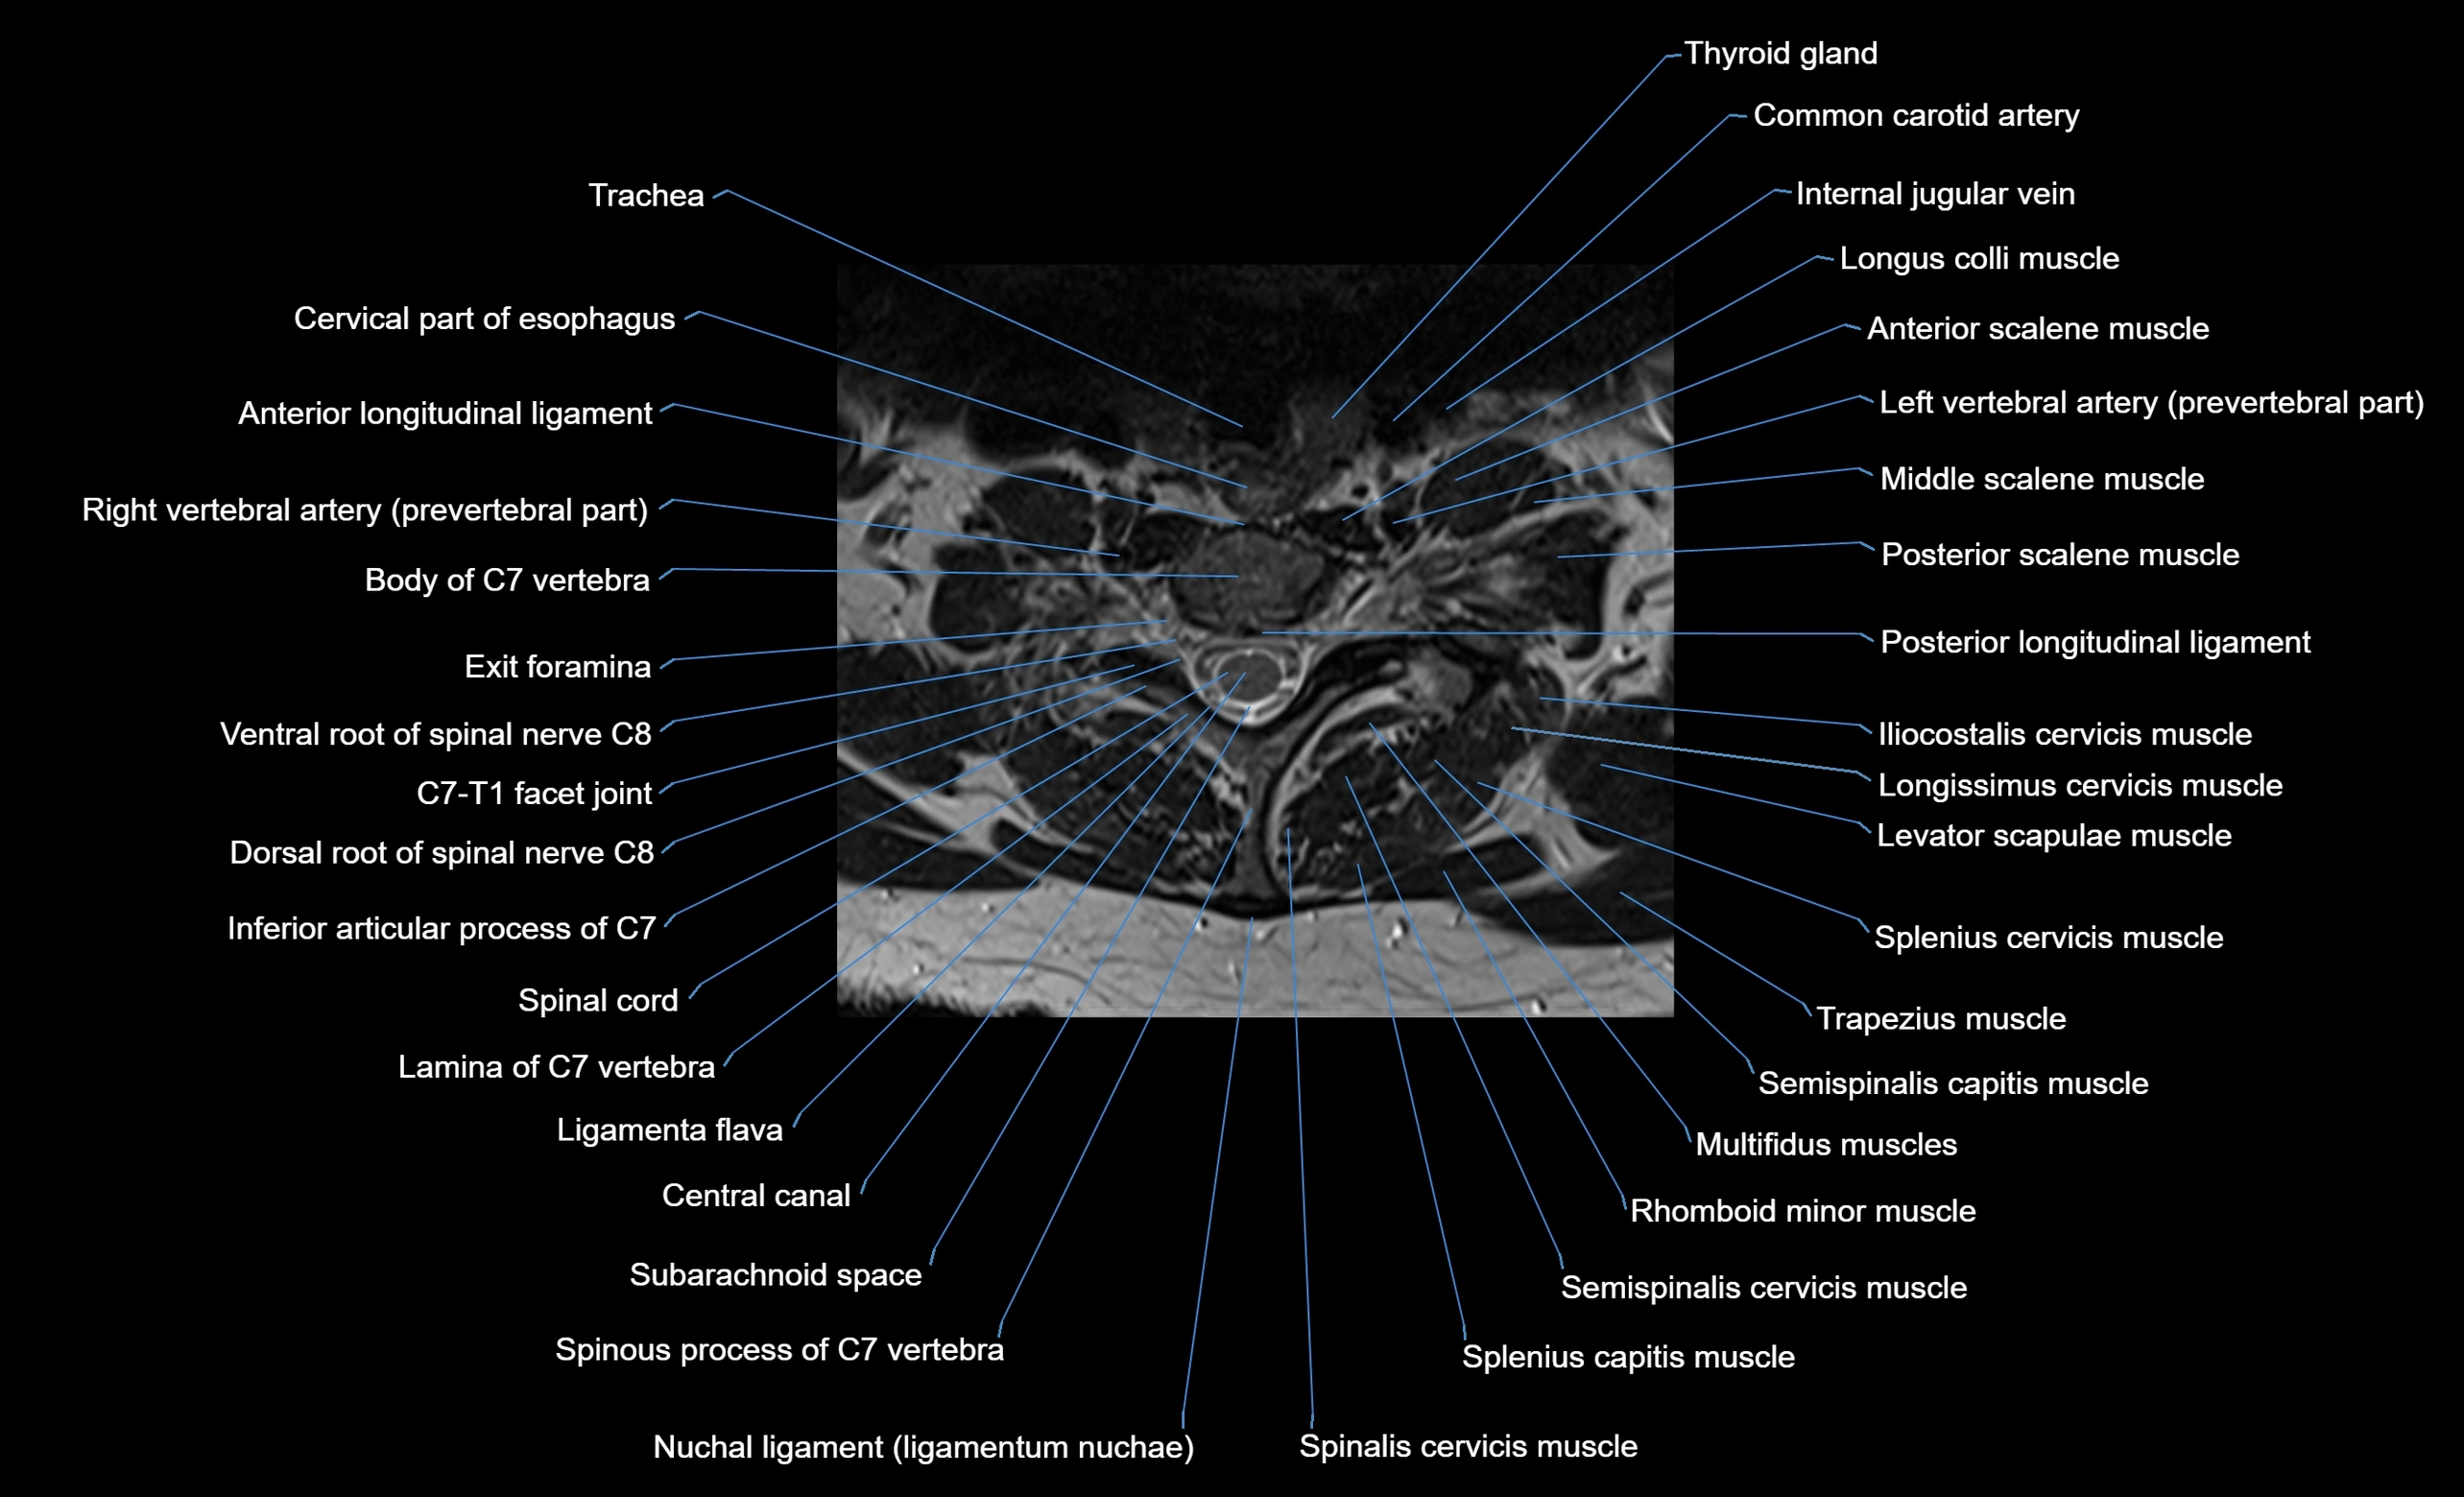

MRI image

image